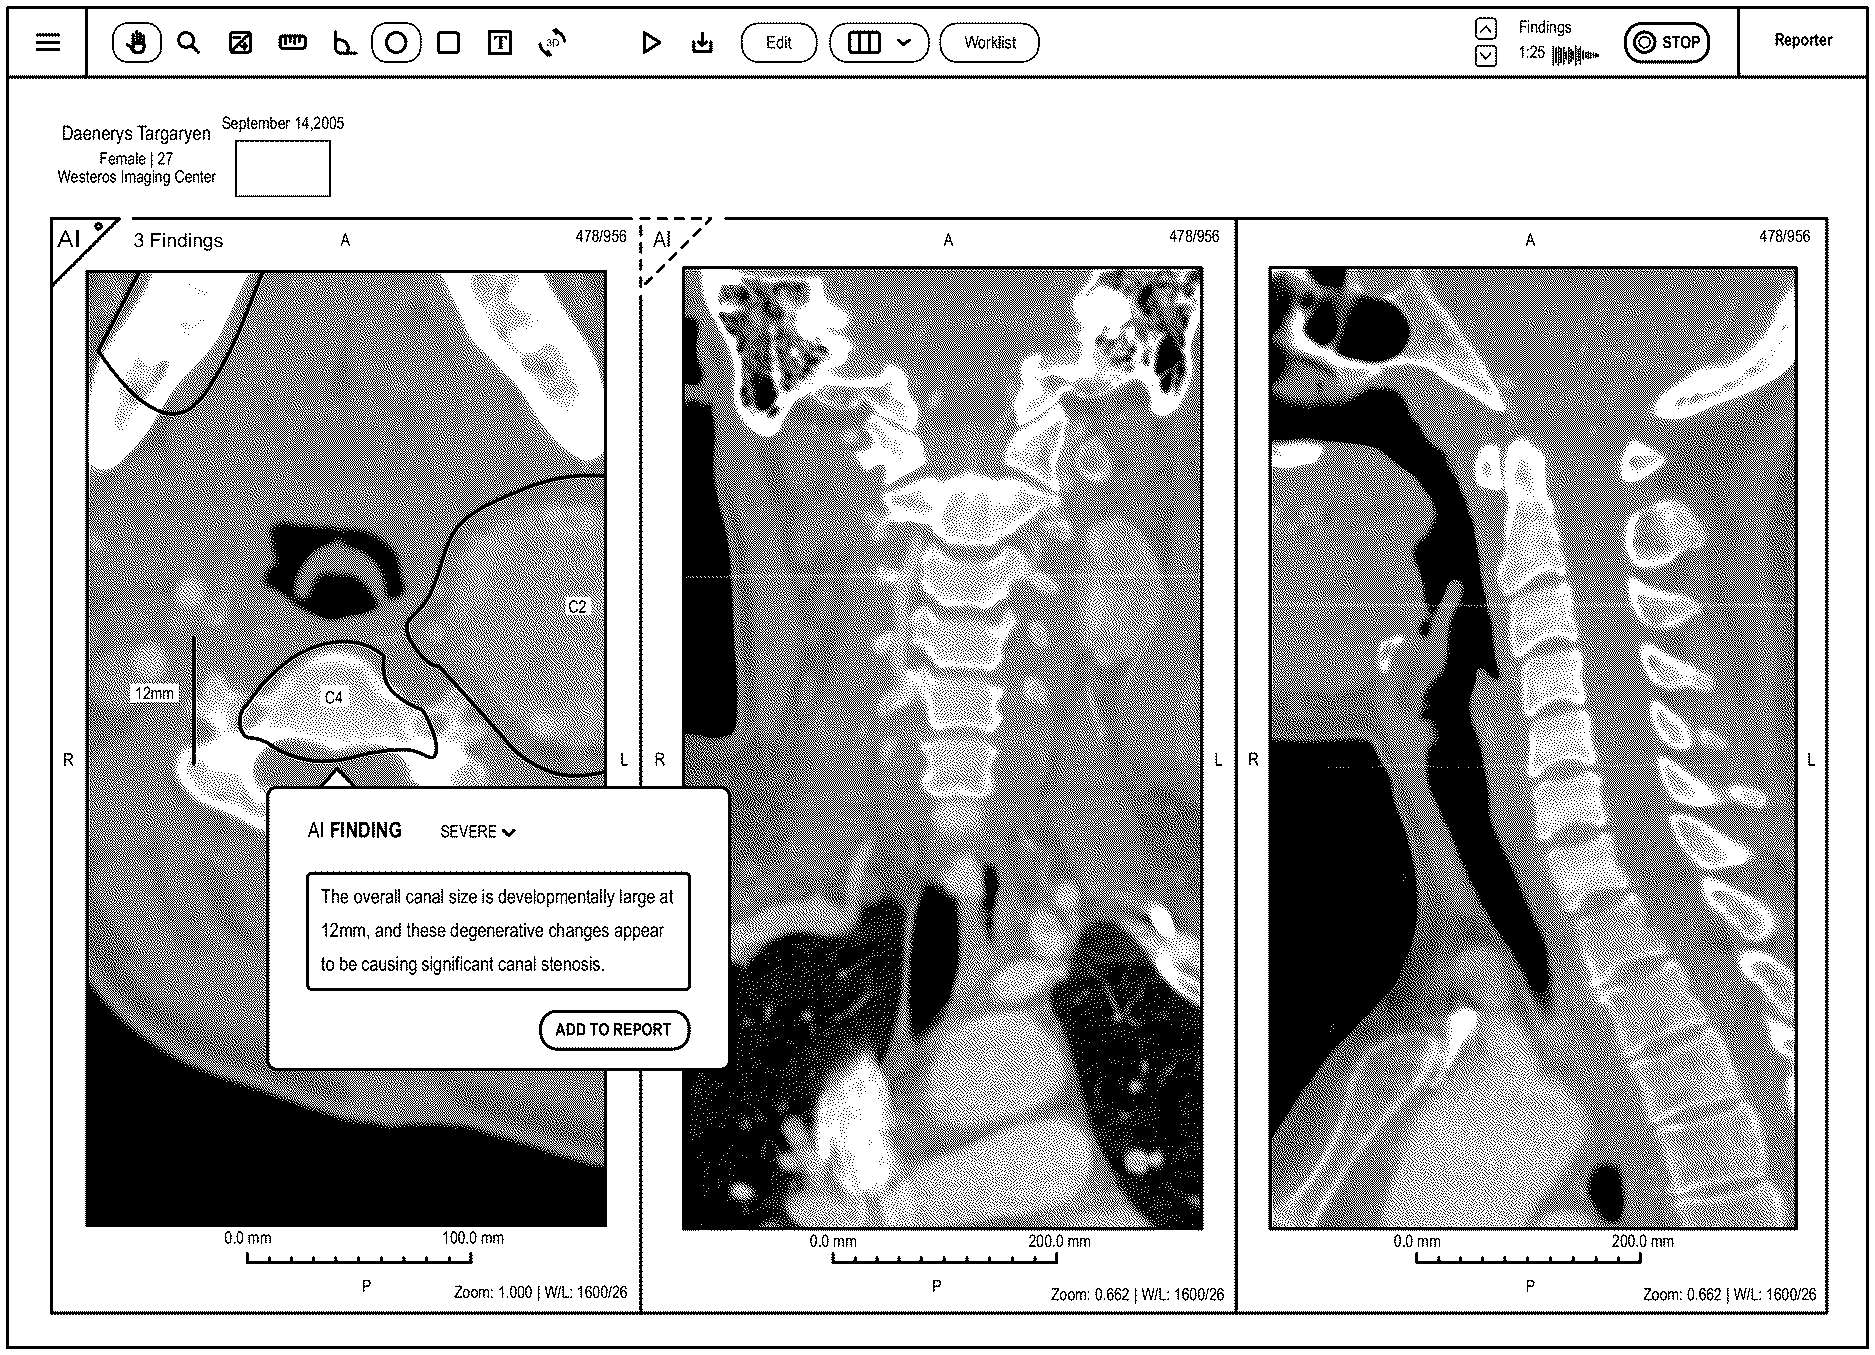

Disclosed herein are systems, methods, and software for providing a platform for artificial intelligence-assisted image analysis.

1.-88. (canceled) 89. A computer-based system for displaying a medical report, comprising:

(a) a processor; (b) a display; (c) a non-transitory computer readable storage medium encoded with a computer program that causes said processor to:

display a medical image on said display, wherein said medical image comprises an anatomic structure; generate a link corresponding to said anatomic structure; and display said medical report comprising said link, wherein said selection of said link retrieves said medical image for viewing. 90. The system of 91. The system of 92. The system of 93. The system of 94. The system of 95. The system of 96. The system of 97. The system of 98. The system of 99. The system of 100. The system of 101. The system of 102. The system of 103. The system of 104. The system of 105. The system of 106. The system of 107. The system of generate said link corresponding to said coordinate of said medical image. 108. The system of 109. The system of